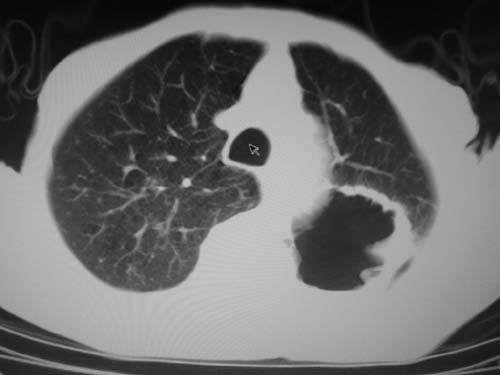

标题: CT19736:男,76岁,咳嗽,胸痛 [打印本页]

标题: CT19736:男,76岁,咳嗽,胸痛

周围型肺癌?坏死性肉芽肿?

支持左上肺周围型肺癌性并空洞形成伴胸椎转移。

左上沟癌空洞形成并胸椎转移。

考虑癌性空洞并胸椎转移。

空洞内壁有多发结节,支持癌性空洞。